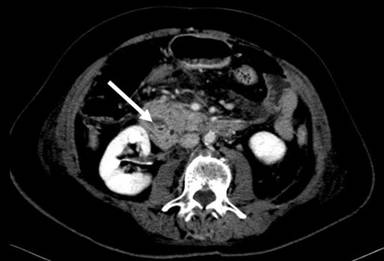

A 72-year-old female presented with acute epigastric pain radiating to her back, associated with nausea and vomiting. There was no associated hematemesis, jaundice or fever. The following illnesses were of note in her medical history: a cholecystectomy (for biliary colic attacks), hypertension and osteoarthritis. She was taking 100 mg/day of atenolol and 2 g/day of paracetamol. She abstained from all alcohol consumption. On examination, she appeared to be in pain and was dehydrated. Her abdomen was supple with epigastric tenderness. Laboratory examination revealed leukocytosis (11,500 mm-3; reference range: 4,000-10,000 mm-3). Pancreatic enzymes were abnormally increased (lipase: 956 IU/L, reference range: 114-286 IU/L; amylase: 765 IU/L, reference range: 25-115 IU/L). Hepatic enzymes, calcemia and triglyceridemia were all within the normal range and there was no biological cholestasis. An abdominal CT-scan confirmed the diagnosis of acute pancreatitis (Balthazar computed tomography grading system C) and revealed a ring of inflammatory tissue surrounding the second duodenum which was isodense with pancreatic tissue, leading to the diagnosis of annular pancreas (Figures 1 and 2). The biliary ducts were not dilated and no residual stones were seen in the bile ducts at MR cholangiography and endoscopic ultrasound. Double-contrast barium radiography showed stenosis of the second duodenum associated with proximal dilation of the duodenal bulb and stomach, classically known as the “double bubble” sign (Figure 3). An endoscopic biopsy of the stenotic portion of the duodenum was performed and did not reveal any tumoral tissue. In view of these findings, the diagnosis of acute pancreatitis secondary to annular pancreas was confirmed. The duodenal occlusion was related to the stenosis of the second duodenum caused by the pancreatitis. Medical treatment based on her symptoms was then begun. The treatment progressively reduced the pain and no complications occurred. After three weeks of nasojejunal liquid feeding, the patient was again able to eat solid food and she was then discharged. In light of the patient’s age, and the fact that it was her first clinical manifestation of acute pancreatitis related to annular pancreas, a Whipple’s procedure was not indicated.

Figure 1. Abdominal CT scan: a ring of inflammatory tissue surrounding the second duodenum (arrow) leading to the diagnosis of annular pancreas and acute pancreatitis confined to the annulus and the adjoining pancreatic head. |